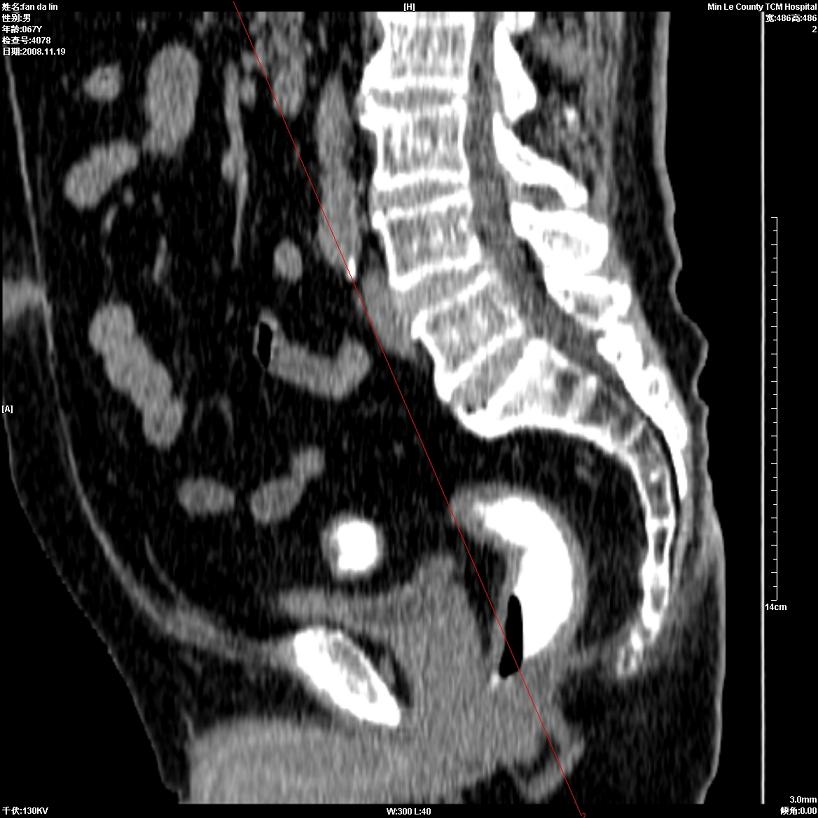

标题: CT16698:M67Y,看看直肠下端是不是病变 [打印本页]

标题: CT16698:M67Y,看看直肠下端是不是病变

直肠及乙状结肠管壁均增厚,考虑炎症.

直乙交界处肠壁不规则增厚,还是做个肠镜吧

只是肠壁局限性增厚,但难说明问题。